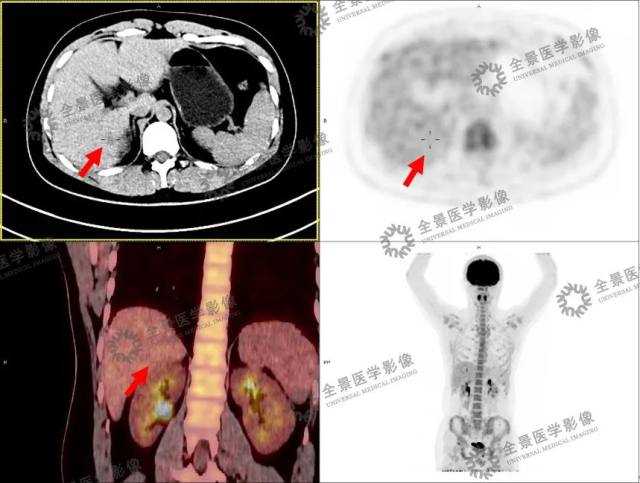

PET/CT 影像资料

肝右后叶下段稍低密度小结节,FDG 本底摄取。

PET/CT 影像结果出来后,MIP 图像未见明显异常 FDG 代谢灶,再加上患者这么年轻,很难让人将他与「癌症」联系到一起。

然而一步步仔细观察图像以后,医生们发现了可疑病灶——患者肝脏上有一个 1 cm 的稍低密度病灶,FDG 本底摄取,肿瘤性病变可疑,但由于病灶过小,很难诊断其到底是良性还是恶性。